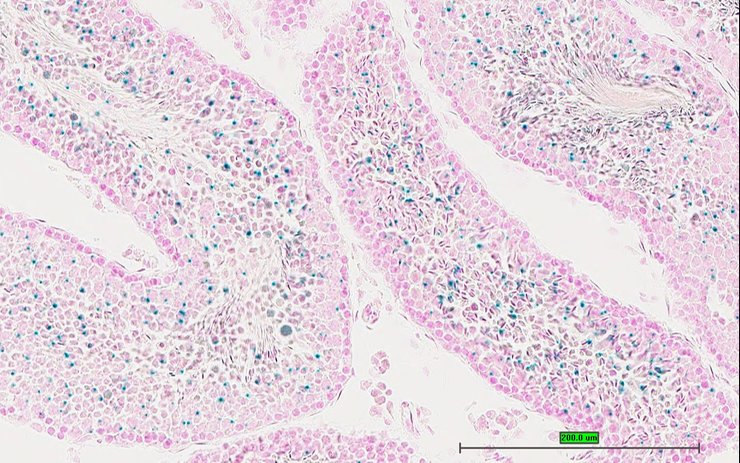

TS28: testis Present UC Davis_1879139

Specimen UC Davis_1879140: postnatal adult; Cnnm2tm1.1(KOMP)Vlcg/Cnnm2+ (more )

Structure Level Pattern Image Note

TS28: epididymis Present UC Davis_1879140